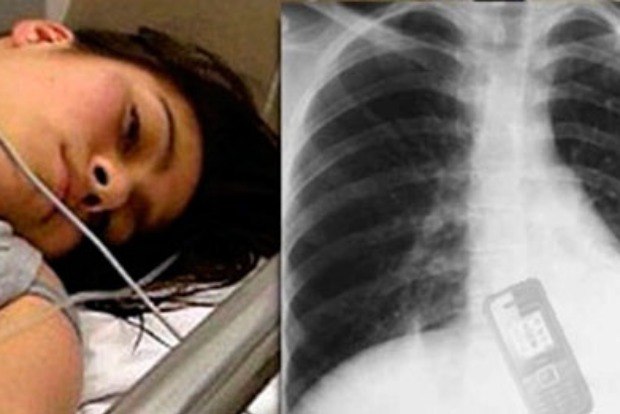

raio-x da menina -  reprodução internet

Uma jovem de 19 anos foi submetida a uma cirurgia de emergência após engolir um telefone celular. Adriana Andrade, moradora da zona leste de São Paulo, não queria que o namorado lesse as mensagens de texto que poderiam comprometer o relacionamento dos dois.

De acordo com os médicos, Adriana não corre risco de vida. No entanto, ela ficará alguns dias internada. Até agora, ninguém sabe o real conteúdo das mensagens.